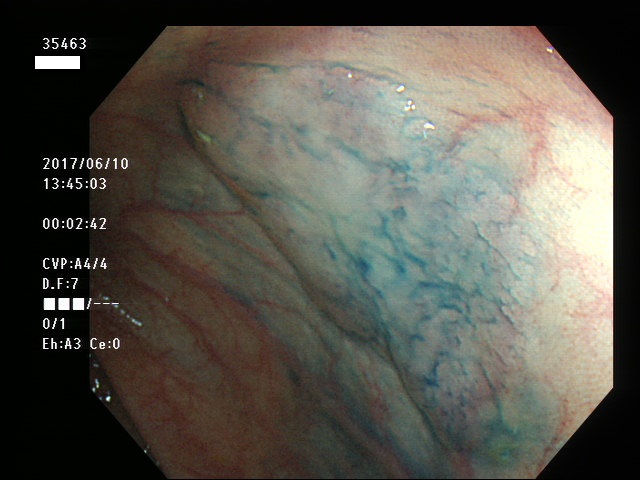

上記100名より抽出した平坦・陥凹型腺腫・SSAP(=癌化の危険が高いが見落としやすい病変)の内視鏡写真

35403 35404 35405 35409 35410 35412 35413 35414 35416 35417 35418 35419 35420 35421 35426 35429 35430 35433 35434 35435 35438 35439 35440 35444 35445 35447 35449 35450 35451 35452 35453 35454 35458 35460 35463 35464 35466 35468 35469 35470 35472 35473 35478 35479 35481 35483 35485 35489 35490 35491 35492 35493 35498 ・・・・・の54名